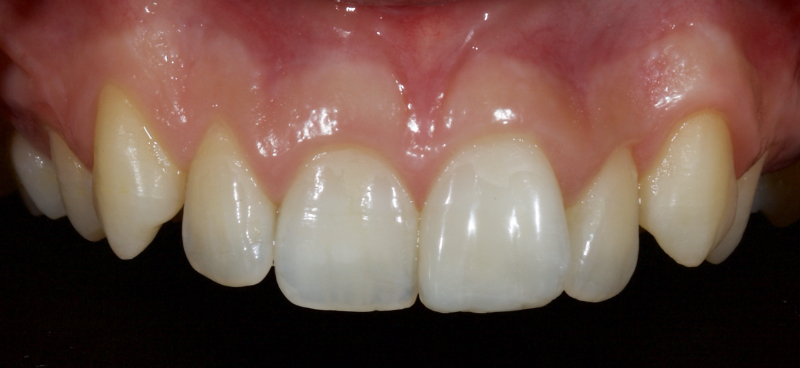

Historically, discolored anterior teeth were treated with indirect ceramic restorations, such as crowns or veneers. This can be illustrated in the case shown in Figure 1, where the discolored left central incisor (2.1), along with two other incisors, was treated with lithium disilicate ceramic veneers (Fig. 2). More recently, direct composite materials that incorporate specialized “opaquers” have also been utilized for treatment.